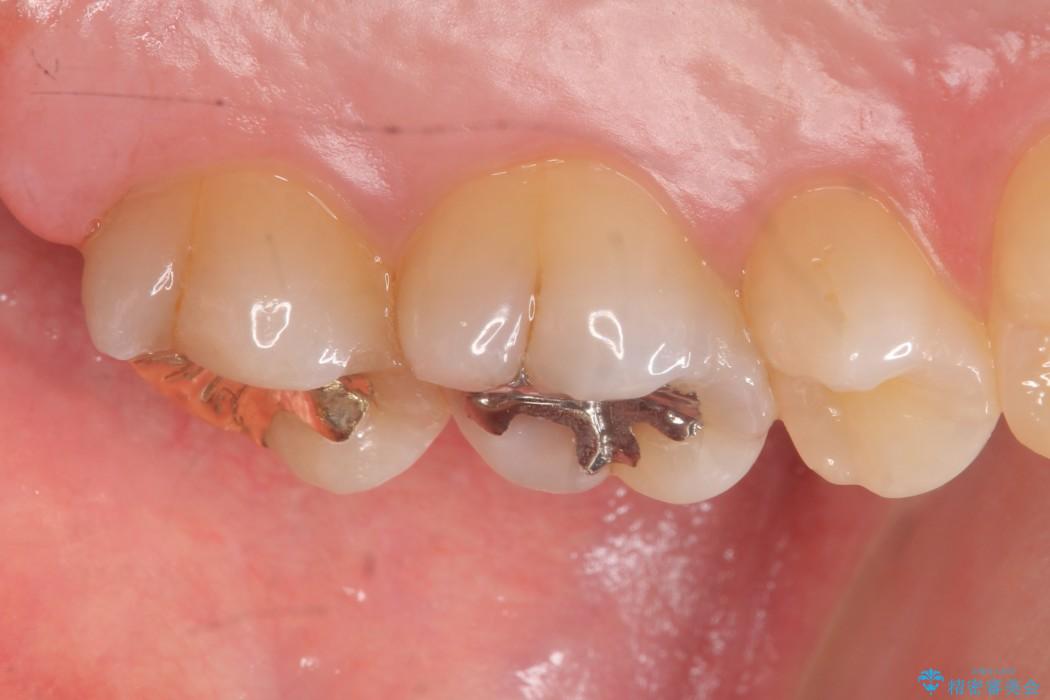

食事中に歯が欠けてしまったとのことで来院されました。

上顎左の一番奥の歯が深い虫歯になって脆くなり、更にその状態に強く噛みしめたわけではない通常の咬合力が加わったことで歯が欠けてしまっていました。